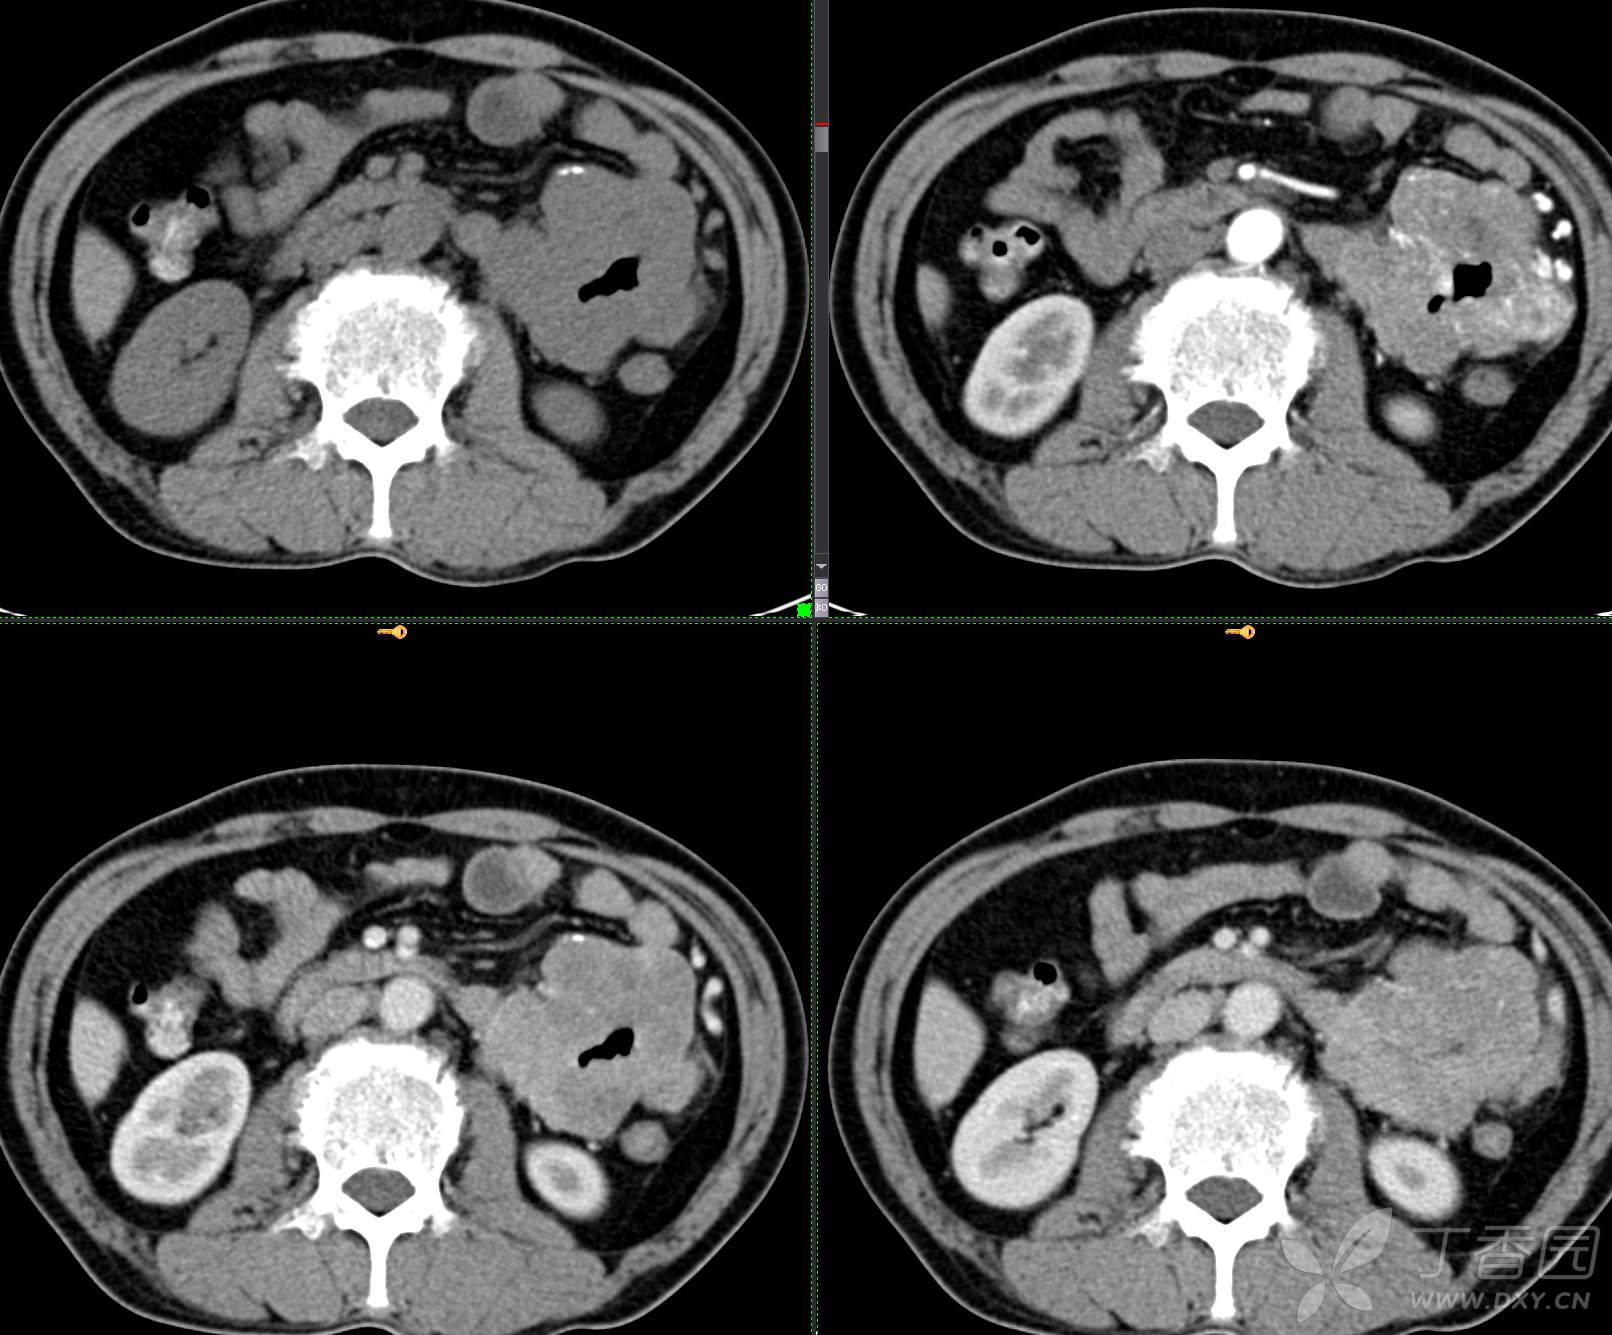

讨论:小肠病变,间质瘤?淋巴瘤?小肠腺癌?